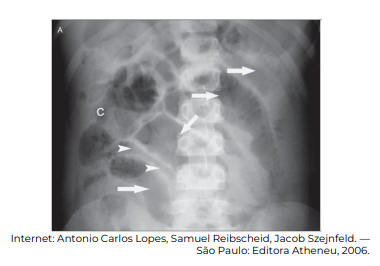

Considerando a interpretação radiológica abdominal no pós-operatório, bem como as patologias cirúrgicas do abdome, de acordo com a imagem — “C” denota-se cólon —, o sinal presente é denominado